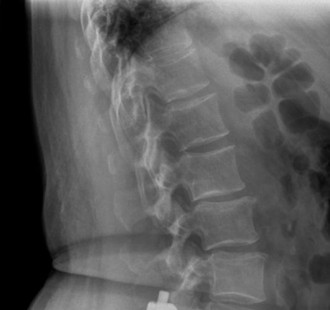

Prognosis of central cord syndrome? Indications for surgery for this disorder? CASE 2 A 56-year-old man presents to you with a chief complaint of severe right buttock, posterior thigh, and lower leg pain for 12 weeks. It radiates to the lateral aspect of his foot, and it is worse with sitting or standing for prolonged periods and with walking. Now over the past 2 weeks, he reports difficulty with toe push-off on the right side. Treatment so far has been nonsteroidal anti-inflammatory drugs (NSAID), physical therapy, and an epidural injection without significant relief. Physical examination findings include 4/5 right ankle plantar flexion, a positive straight leg raise on the right, and an absent right Achilles tendon reflex. Images of his lumbar spine are shown in Figures 1–4 and 1–5.

Figure 1–4

The correct answer is (C). The patient presents with classic right S1 radiculopathy and new onset plantar flexion weakness. The images demonstrate a right-sided paracentral disc herniation at L5/S1 compressing the traversing S1 nerve root. Despite nonoperative management, he continues to have severe pain and new weakness. Continued physical therapy or an epidural injection is unlikely to improve the patient’s pain at this time. In the setting of neurological decline, surgery is more strongly indicated. Lumbar discectomy is the most appropriate procedure for this patient. Fusion would only be indicated if there were radiographic signs of instability, which are not present.